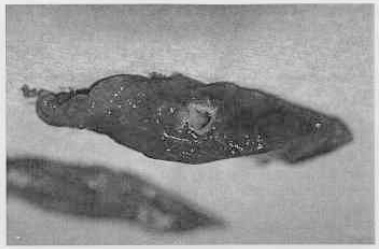

気管支拡張症の気道を肉眼観察すると、著明な拡張が明らかであり、膿性分泌物で覆われた表面もよく分かるようになる。(図51−1)肺生検では、病変部の気道の拡張が明らかになる。また、気道壁がさまざまな程度で肉芽形成と線維化で再構築されている様子が分かる。組織学的には、気道管腔は、粘液、蛋白質様物質、および炎症細胞(図51−2)で通常満たされている。[1,2,4] 肺実質中の細胞性浸潤物のタイプおよび量は、基礎疾患に依存する。気管支周囲組織の炎症が普通にみられる。[1,2,4]

図51−1。管腔内に粘液化膿性滲出物を伴って大きく拡張した気道(気管支拡張症)を示す犬からの肺生検。この犬は慢性の好酸球性気管支炎に継発した重度のびまん性気管支拡張症を呈していた。